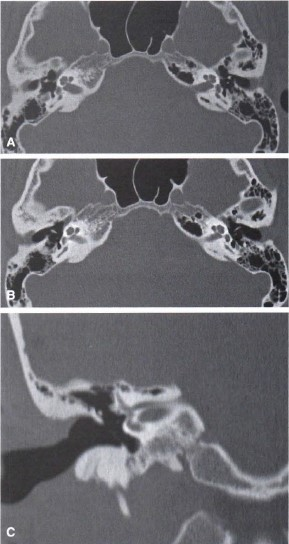

A tomografia computadorizada é um excelente método para a avaliação dos ossos temporais, sobretudo as estruturas do ouvido médio e mastoide. Analisando o ouvido direito mostrado na imagem a seguir, qual anomalia congênita da cadeia ossicular pode ser observada?